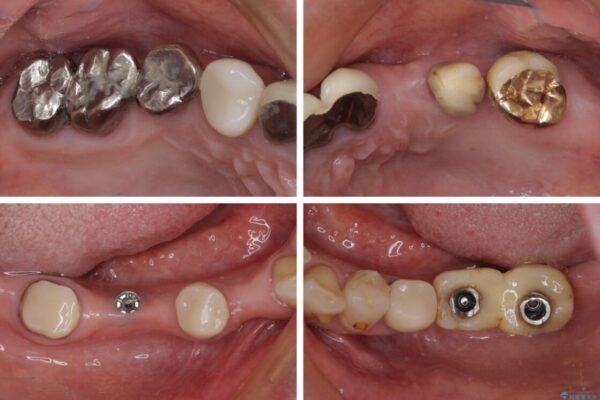

治療前

• 放置したインプラントとインビザライン 全顎リカバリー治療 治療前画像